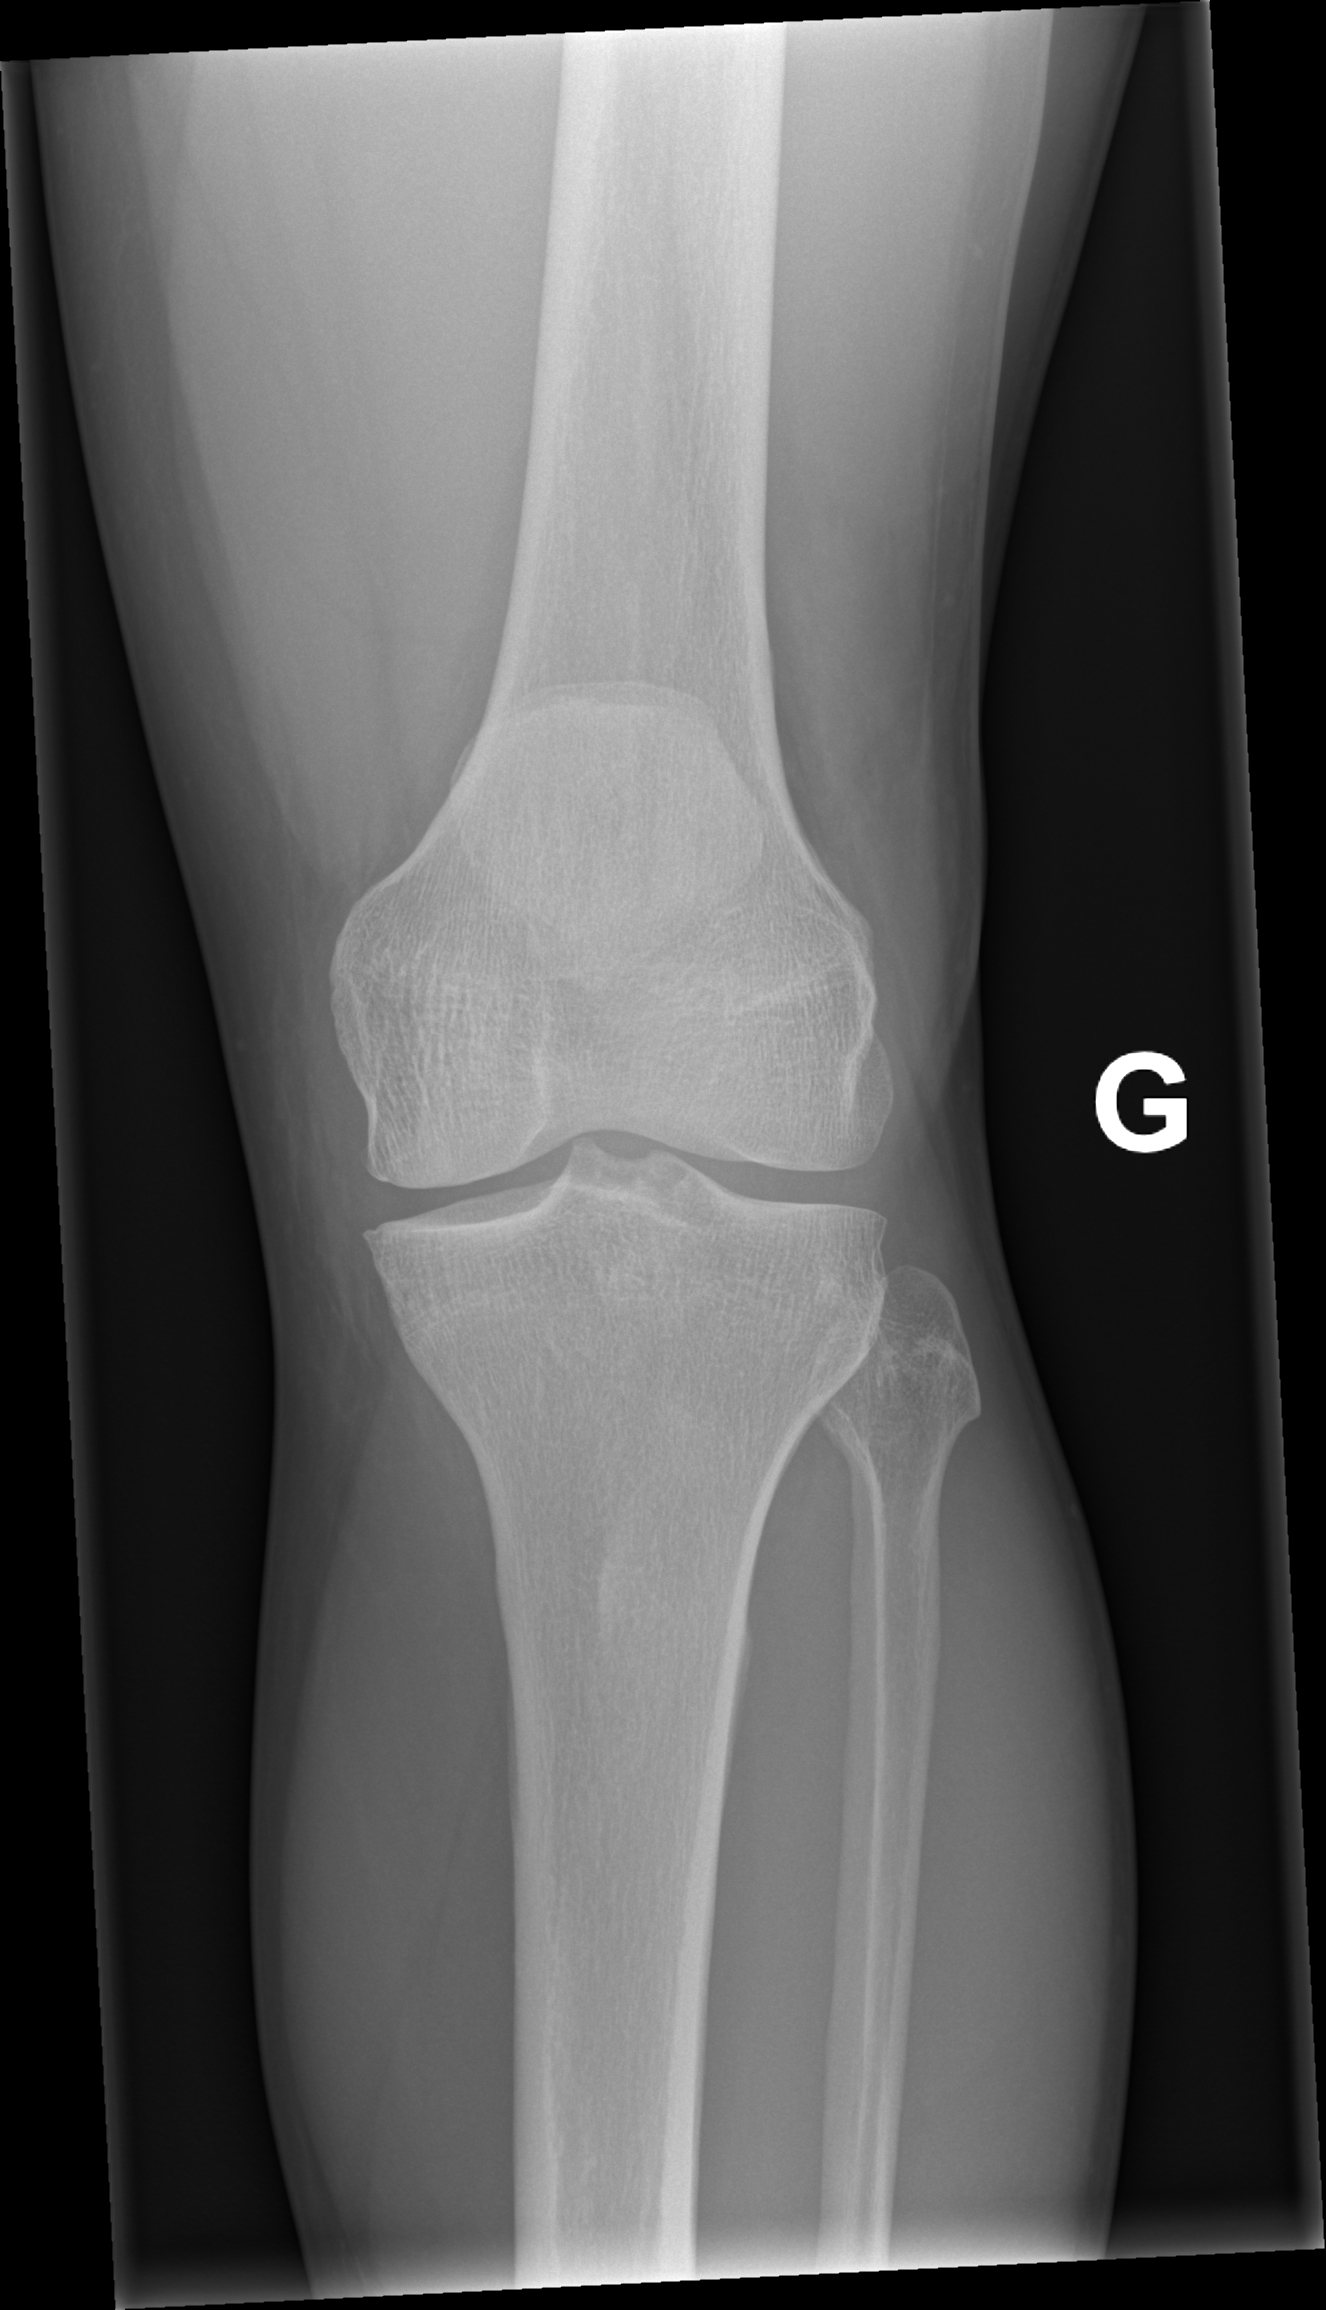

A l’examen clinique, le genou est légèrement tuméfié. La rotule semble ascensionnée et un creux est palpé sur le trajet du tendon rotulien. L’extension active est impossible. Sur les radiographies standards face et profil du genou, la rotule est ascensionnée.

Lorsque l’incidence axiale (ou défilé fémoro-patellaire, genou fléchi à 30°) est réalisée, l’image est décrite comme un « lever de soleil » avec une disparition de l’interligne articulaire et la superposition de la rotule avec les condyles fémoraux.